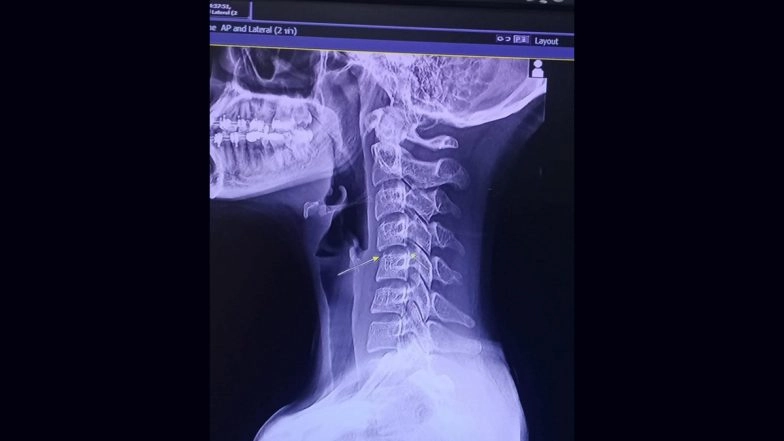

What comes as a surprising revelation after the unfortunate incident is that Chayada Prao-hom's mother was a masseuse, and she herself had studied Thai massages. As per media reports, Prao-hom first visited the parlour in October, where she received massages involving intense neck-twisting techniques. Just two days after her session, Prao-hom complained of pain in her neck. However, things got even worse after she went for a second session, where the existing pain had more severe effects on her body as well. There was stiffness throughout her body.

Updating her fans and followers about her health in a social media post, she wrote, "I love massages so much that I didn't suspect anything. I thought this was simply a side effect of getting another massage." By mid-November, Prao-hom was gradually forced to be bedridden as more than 50% of her body became paralyzed. She was admitted to the hospital after her condition deteriorated and later died from complications caused by a blood infection and brain swelling. Saafir Dies at 54; Xzibit Mourns Loss of the ‘Golden State’ Rapper (View Post).